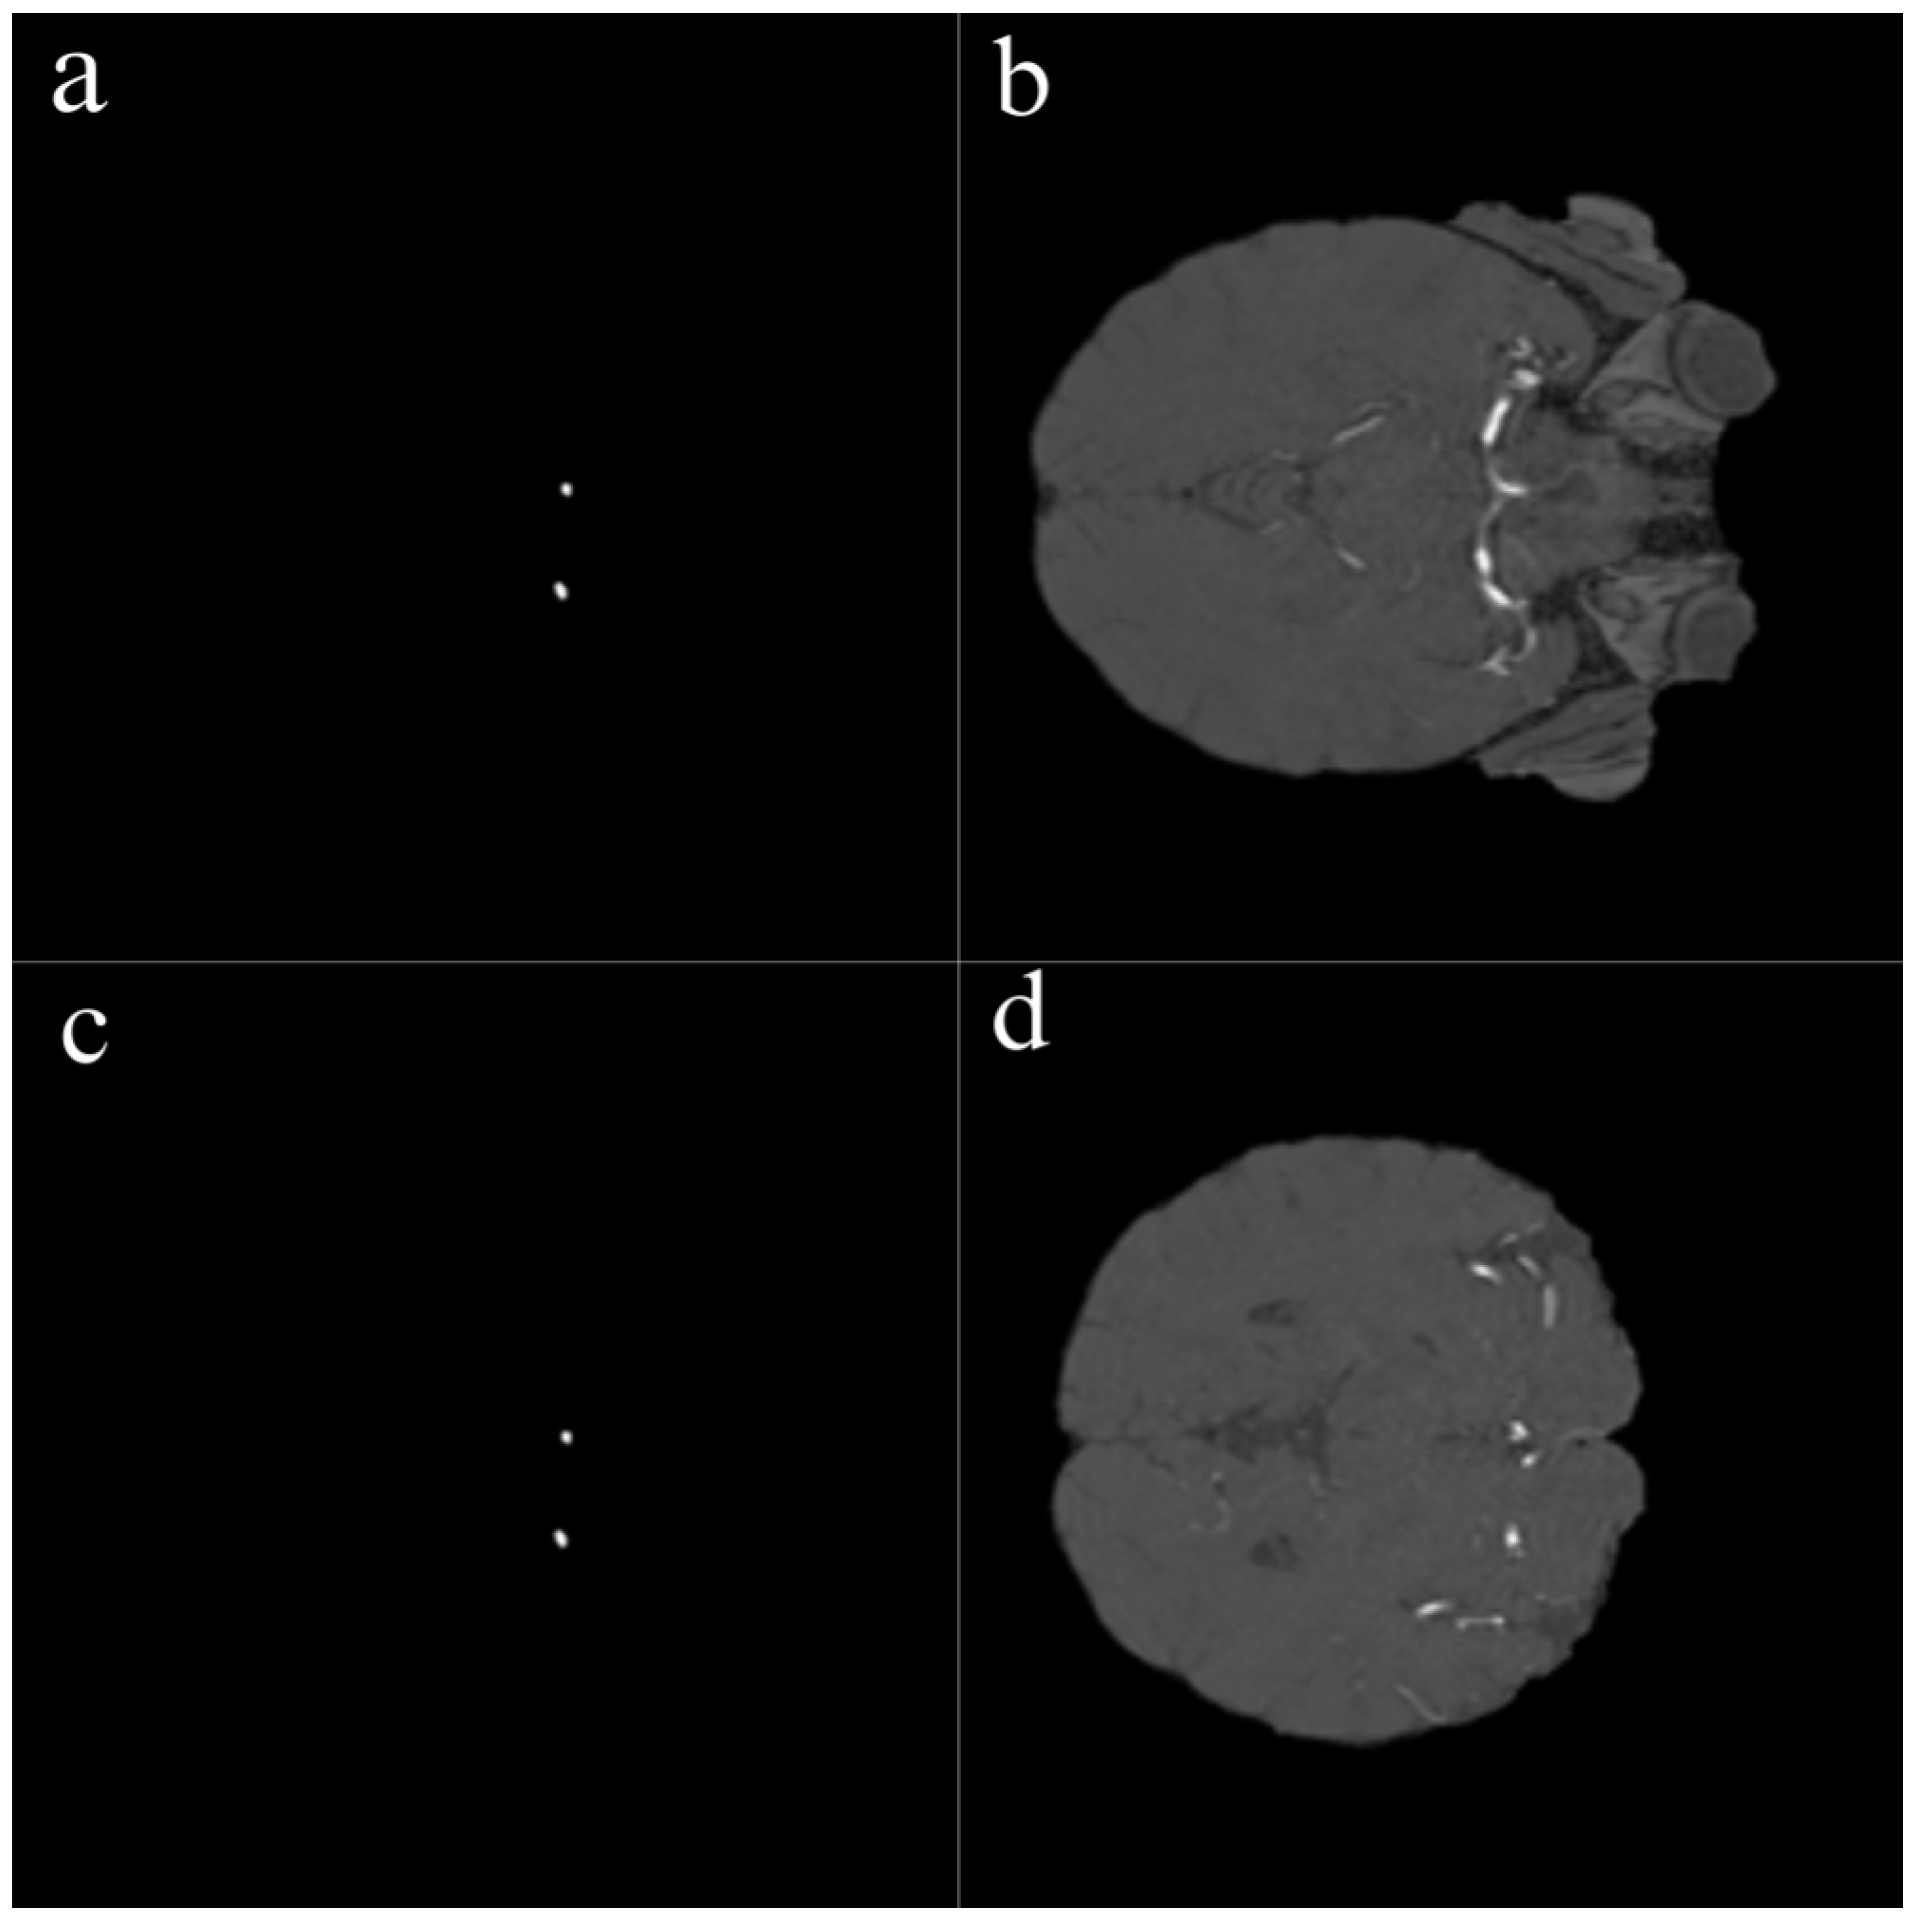

In this study, several preprocessing steps were applied to prepare the TOF-MRA images for deep learning. To focus the model on intracranial structures, skull stripping was applied to all TOF-MRA images using FMRIB’s Brain Extraction Tool (BET). By adjusting parameters such as fractional intensity and surface inflation, brain tissue was effectively isolated. Processed images were manually reviewed, and necessary adjustments were made to ensure accurate brain extraction, resulting in a clean dataset suitable for segmentation. The raw data consisted of 3D volumetric brain images stored in NIfTI format (nii/nii.gz). To improve the training performance of the model and standardize the dataset, these volumes were converted into two-dimensional (2D) slices and saved in PNG format. Each image slice was then paired with its corresponding segmentation mask (Figure 2).

One of the most important steps in the preprocessing workflow was the conversion of 3D volumetric TOF-MRA images into two-dimensional slices. Each TOF-MRA sequence was sliced in the axial plane and converted into 2D images, with each slice saved as an individual image file. The same process was applied to the segmentation masks, ensuring that each aneurysmal region was paired with the corresponding 2D image.

Figure 2. Sample 2D slices and corresponding aneurysm masks derived from TOF-MRA volumes. Left (a,c): Binary segmentation masks showing aneurysm regions in white. Right (b,d): Original TOF-MRA slices corresponding to each mask. Each 3D volume was converted into 2D axial slices, and manual annotations were used to generate ground truth segmentation masks.